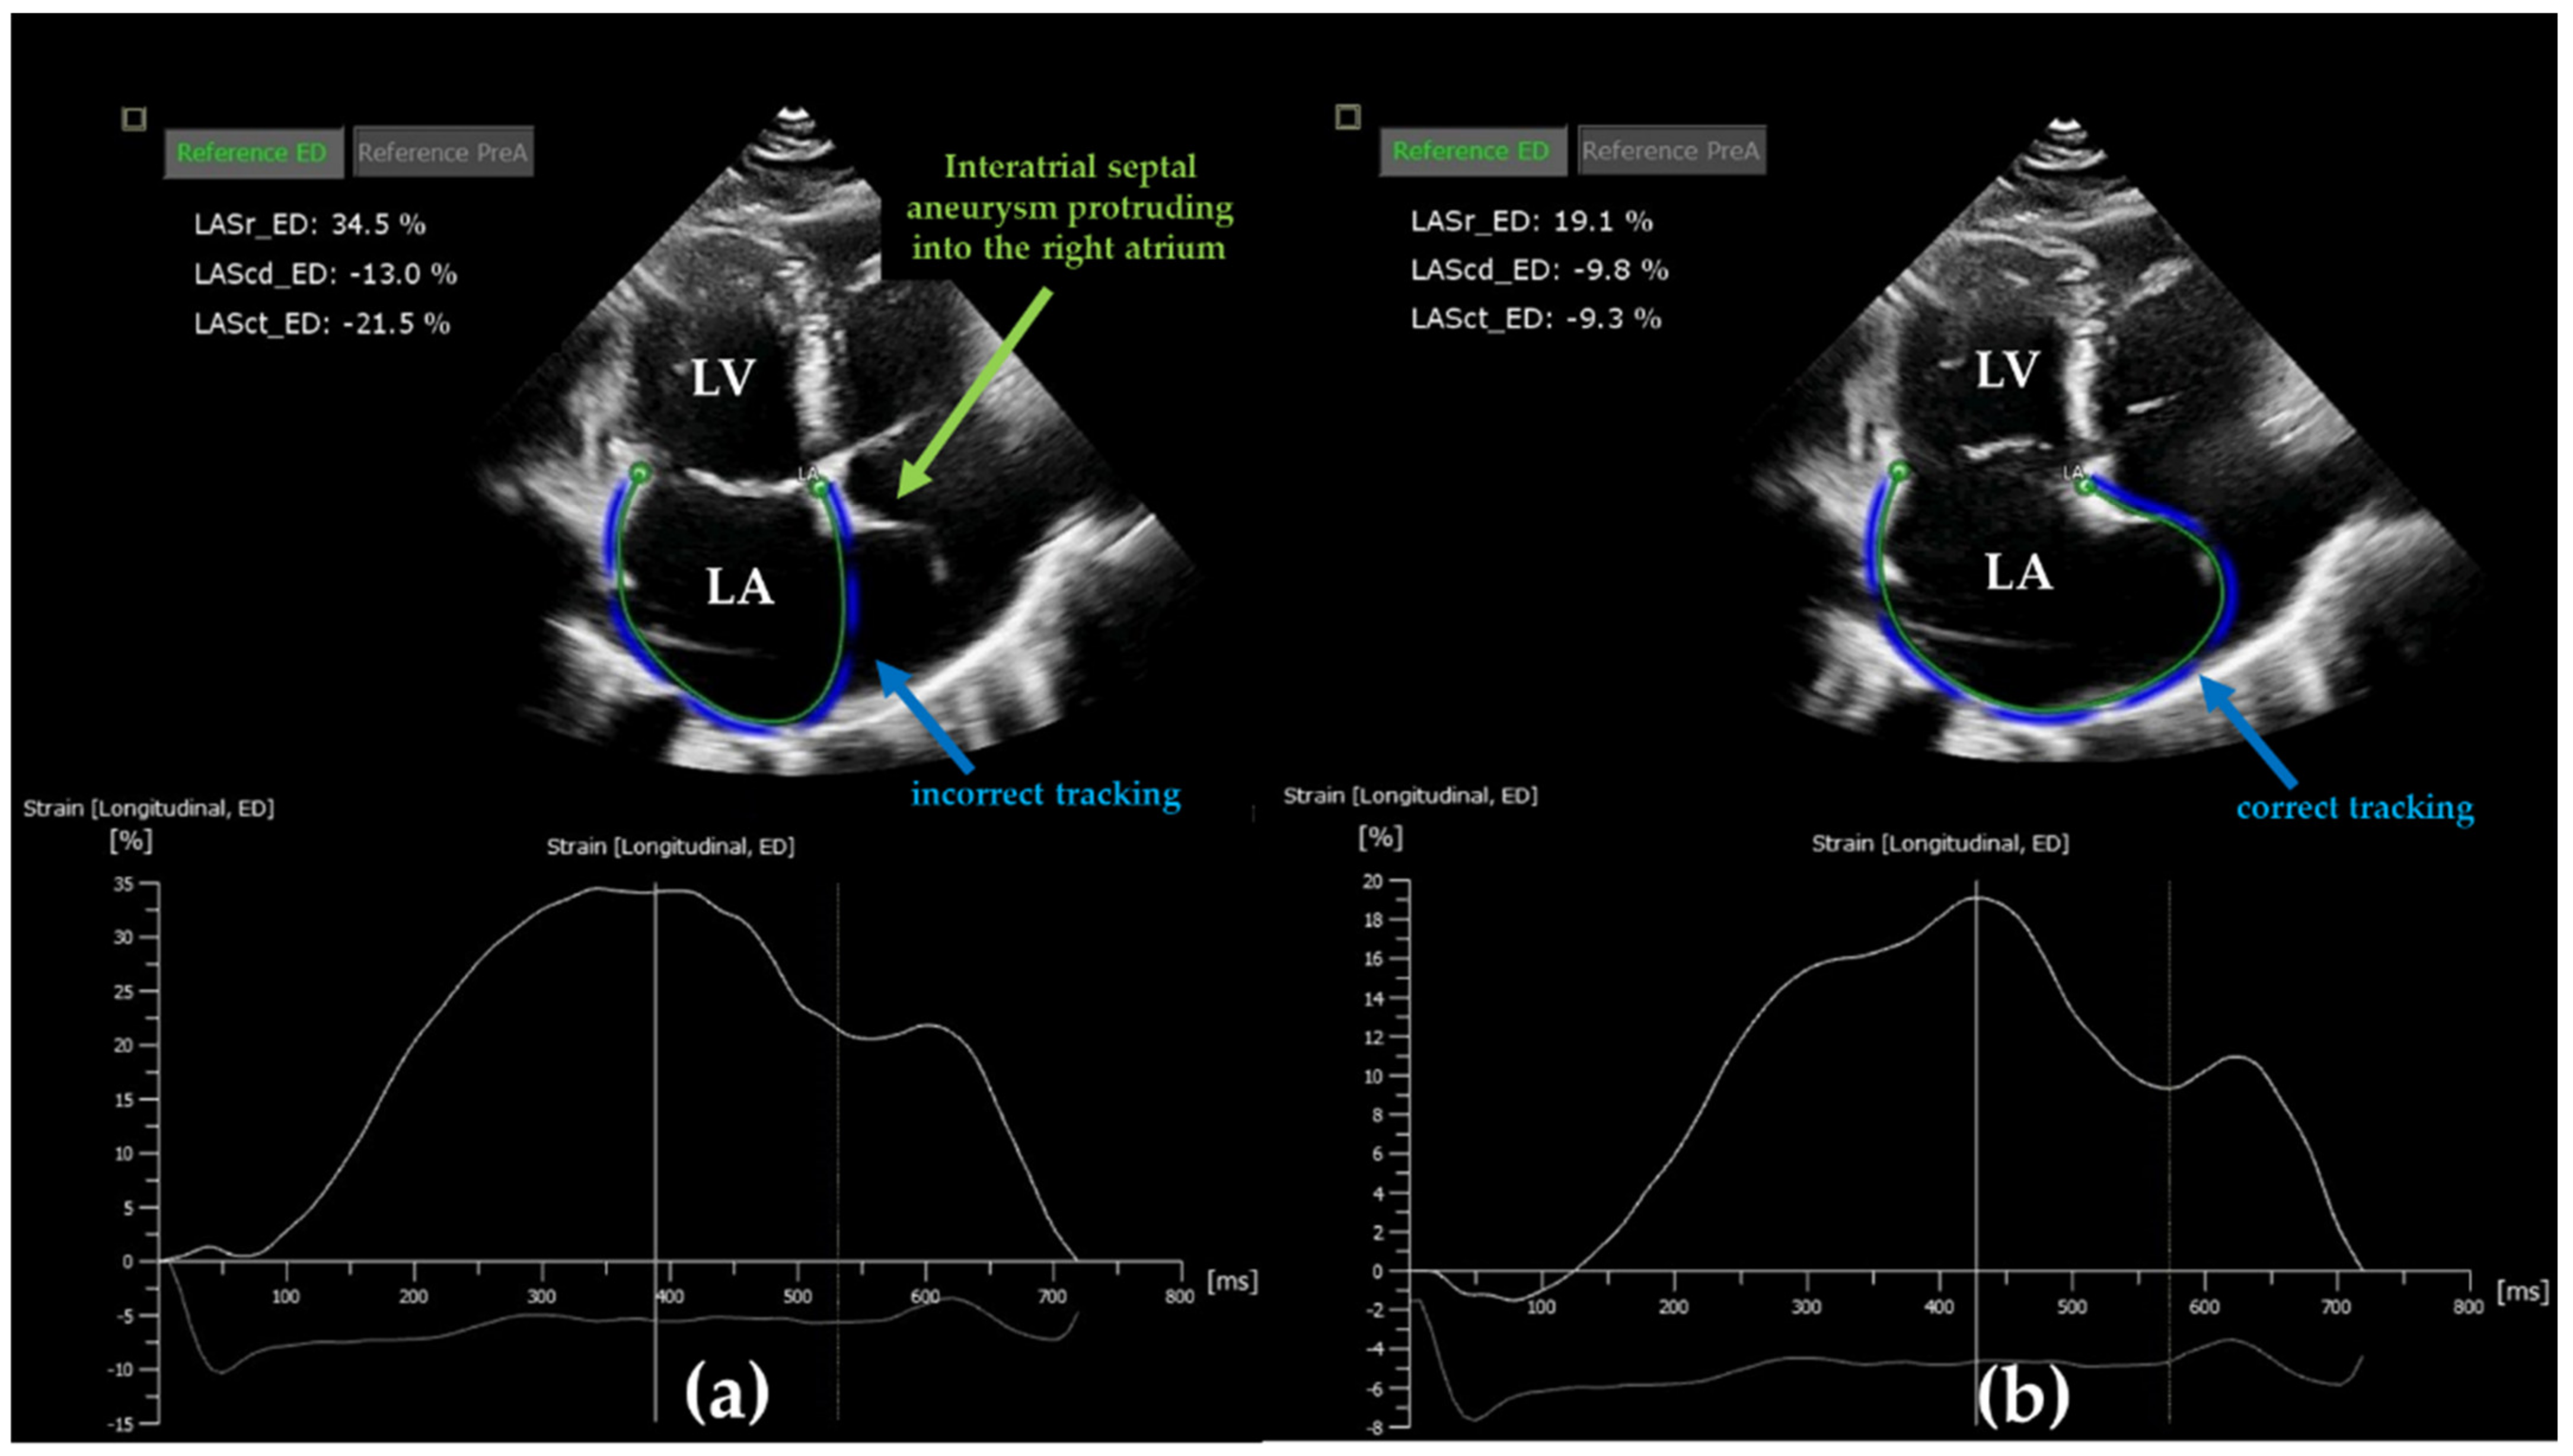

2. Speckle Tracking Echocardiography Method to Assess Left Atrial Function

- Voigt, J.-U.; Mălăescu, G.-G.; Haugaa, K.; Badano, L. How to do LA strain. Eur. Heart J. Cardiovasc. Imaging 2020, 21, 715–717. [Google Scholar] [CrossRef]